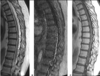

Dx?

Vit B12 deficiency: “inverted V-sign”, bilateral, symmetrically increased T2 signal of the dorsal columns w/o enhancement.

- Aka subacute combined degeneration.

- Typically begins in the upper thoracic region & then either ascends or descends.

- DDx: HIV, ADEM.